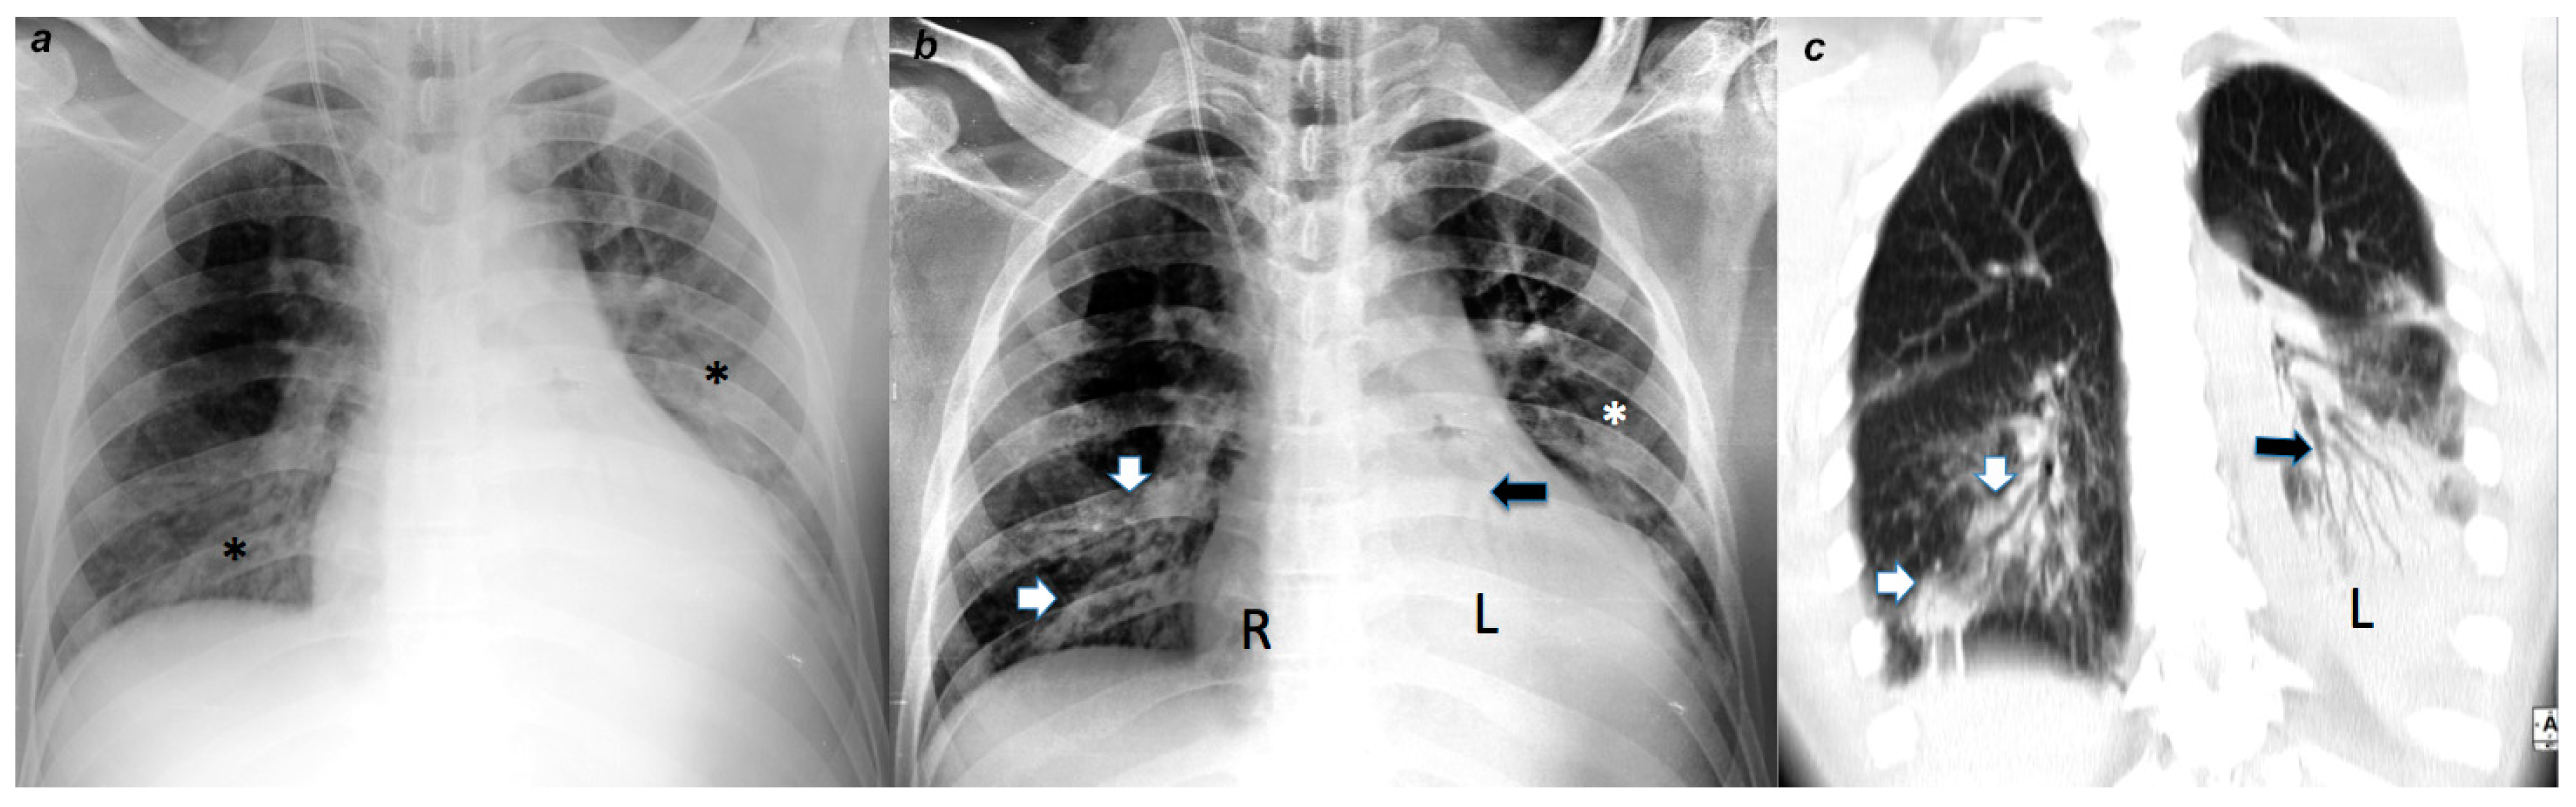

3. Description and Performance Evaluation of the Algorithm

4.2. Radiological Evaluation and Statistics